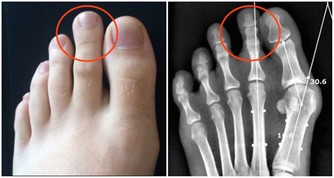

減少尿酸的生成,在生活中主要體現在飲食的調整上,不單單要限制高嘌呤食物的攝入,比如少吃或者不吃海鮮、動物的內臟,少和白酒啤酒等,還要少吃高糖、高脂肪的食物。因為血樣、血脂和血尿酸之間具有相互促進的作用。